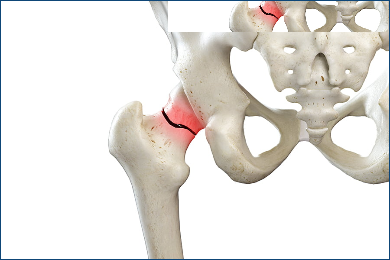

The hip joint is one of the largest and most important joints in the body. It connects the thigh bone to the pelvis and allows for a wide range of motion. However, hip problems and diseases can cause pain, stiffness, and limited mobility, affecting daily life and overall well-being.